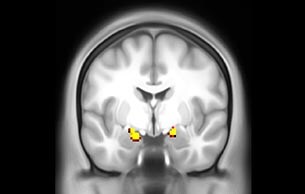

Emotional n-back task combines a test of working memory with the use of emotive (faces) and neutral (places) images. The contrast in the images is between the activity when faces are presented compared to places, showing activation in the amygdala, fusiform, and occipital face areas.

Processing based on the Human Connectome Project (HCP) pipelines. The high resolution of the fMRI data allows extraction of the cortical surface, with minimal averaging of non-cortical signal. Surface based analysis provides improved cross-subject alignment, and prevents signal contamination between adjacent sulci.

Group analysis of 88 9- and 10-year olds part of ABCD, all scanned at UVM on Philips Achieva 3.0T dStream. Scale runs from red p=0.001 to yellow p<10ˆ-5. Images provided by Dr. Watts.

Acquisition using the ABCD protocol for fMRI with TR 800 ms, TE 30 ms, flip angle 52°, 2.4 mm isotropic imaging resolution with a 216×216×144 mm3 field of view using a MultiBand acceleration factor of 6 (60 slices, no gap). Two runs of 5 minutes per subject.